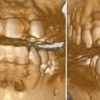

下の歯並びの悪さと、上下の歯のかみ合わせの悪さが、左の前歯の神経を損傷し(咬合性外傷)、歯の神経が壊死し、その後、壊死した歯の神経(歯髄)の中のヘモグロビンが酸化し、歯を黒く変色させ、さらに咬合性外傷が継続して、その歯の損傷を続け、強い咬合力がかかった時に歯の破折を引き起こしたと考えられます。

そのため、もし、その歯の神経の治療(根管治療、歯内療法、歯の神経の治療)を普通に行っても、術後の治癒、予後が悪くなったり、咬合性外傷による歯の損傷が継続し、さらに、外傷性咬合による歯周病(歯槽膿漏)も引き起こすことにつながる可能性が高くなります。

まずは、きちんとした歯の神経の治療(根管治療、歯内療法、歯の神経の治療)を行います。その際、歯の根っこまで、変色した歯のホワイトニングも、見えない基礎治療として行っておきます。